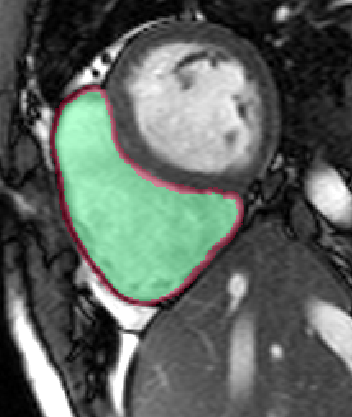

Table 2 summarizes the results of our method for RV segmentation in terms of image-based metrics. The results show that the algorithm performs better at ED than ES. This can be explained by the fact that the image quality is higher at ED than at ES. By analyzing the DM and HD on a slice-basis, it can be seen that the proposed method has a high performance on basal slices, with an average and . However, the segmentations on apical slices are of lower quality affecting the overall DM and HD scores. Figure 3 shows segmentation results in six different cases obtained from the challenge that illustrate the differences between basal and apical segmentations.

The results show that the method perform well on average but there are some cases in which it fails. In particular, our method has a very high performance on the basal slices, whereas the scores obtained for apical slices are lower (Figure 3). These can be explained by two factors: 1) The image quality at the apical slices is rather low. As the registration, the atlas ranking and the label fusion are intensity-based, poor image quality can affect the results, and 2) the regions to be segmented at the apical slices are rather small, which implies that the atlases’ masks are also small at these slices. When the masks are used in the registration process to supress undesired structures, the remaining information is insufficient, causing the intensity-based registration, rigid or non-rigid, to fail.

In conclusion, we have presented a fully automatic segmentation method applied to the extraction of RV epicardium and endocardium. The results show that the method is in average succesful in the segmentation results. The segmentations obtained in the basal slices are of very high quality, whereas the results in the apical ones are less good mainly because the registration stage fails to properly align the atlases with the unseen image.